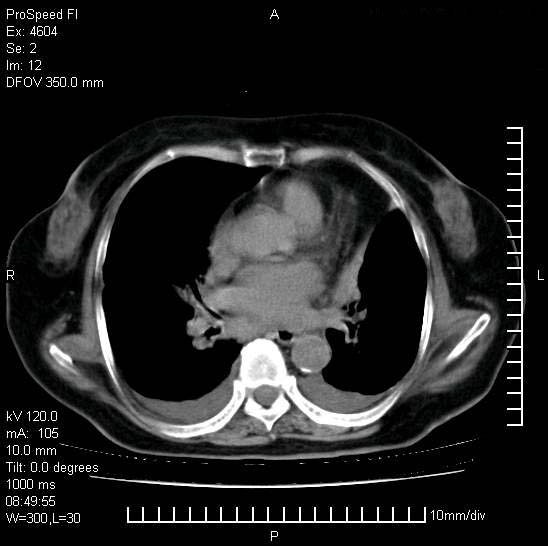

十几年前曾患肺结核,一周前突咳血约100ml,中性粒细胞稍高,诊断两上肺陈旧结核,下肺炎症,给予抗炎治疗,近几日晚上高热,39度,仍咳少量血,4天前ct及今天ct上传。

[face=黑体]8月30日[/face]

今天ct

支持陈旧性肺结核并两下肺感染,两侧胸腔积液。

短短几天内,病变范围明显增多扩大,以左侧明显,而且双侧出现胸水,还是考虑感染.

短短几天内,病变范围明显增多扩大,以左侧明显,而且双侧出现胸水,我更多考虑左侧中心性肺癌并并阻塞性不张及肺炎,炎症变化也太快了!

1)两肺结核并感染。2)不排除左肺上叶中央型肺癌并阻塞性肺炎、肺不张可能;建议行纤支镜检查。3)右肺门及纵隔淋巴结肿大。4)双侧胸腔积液。